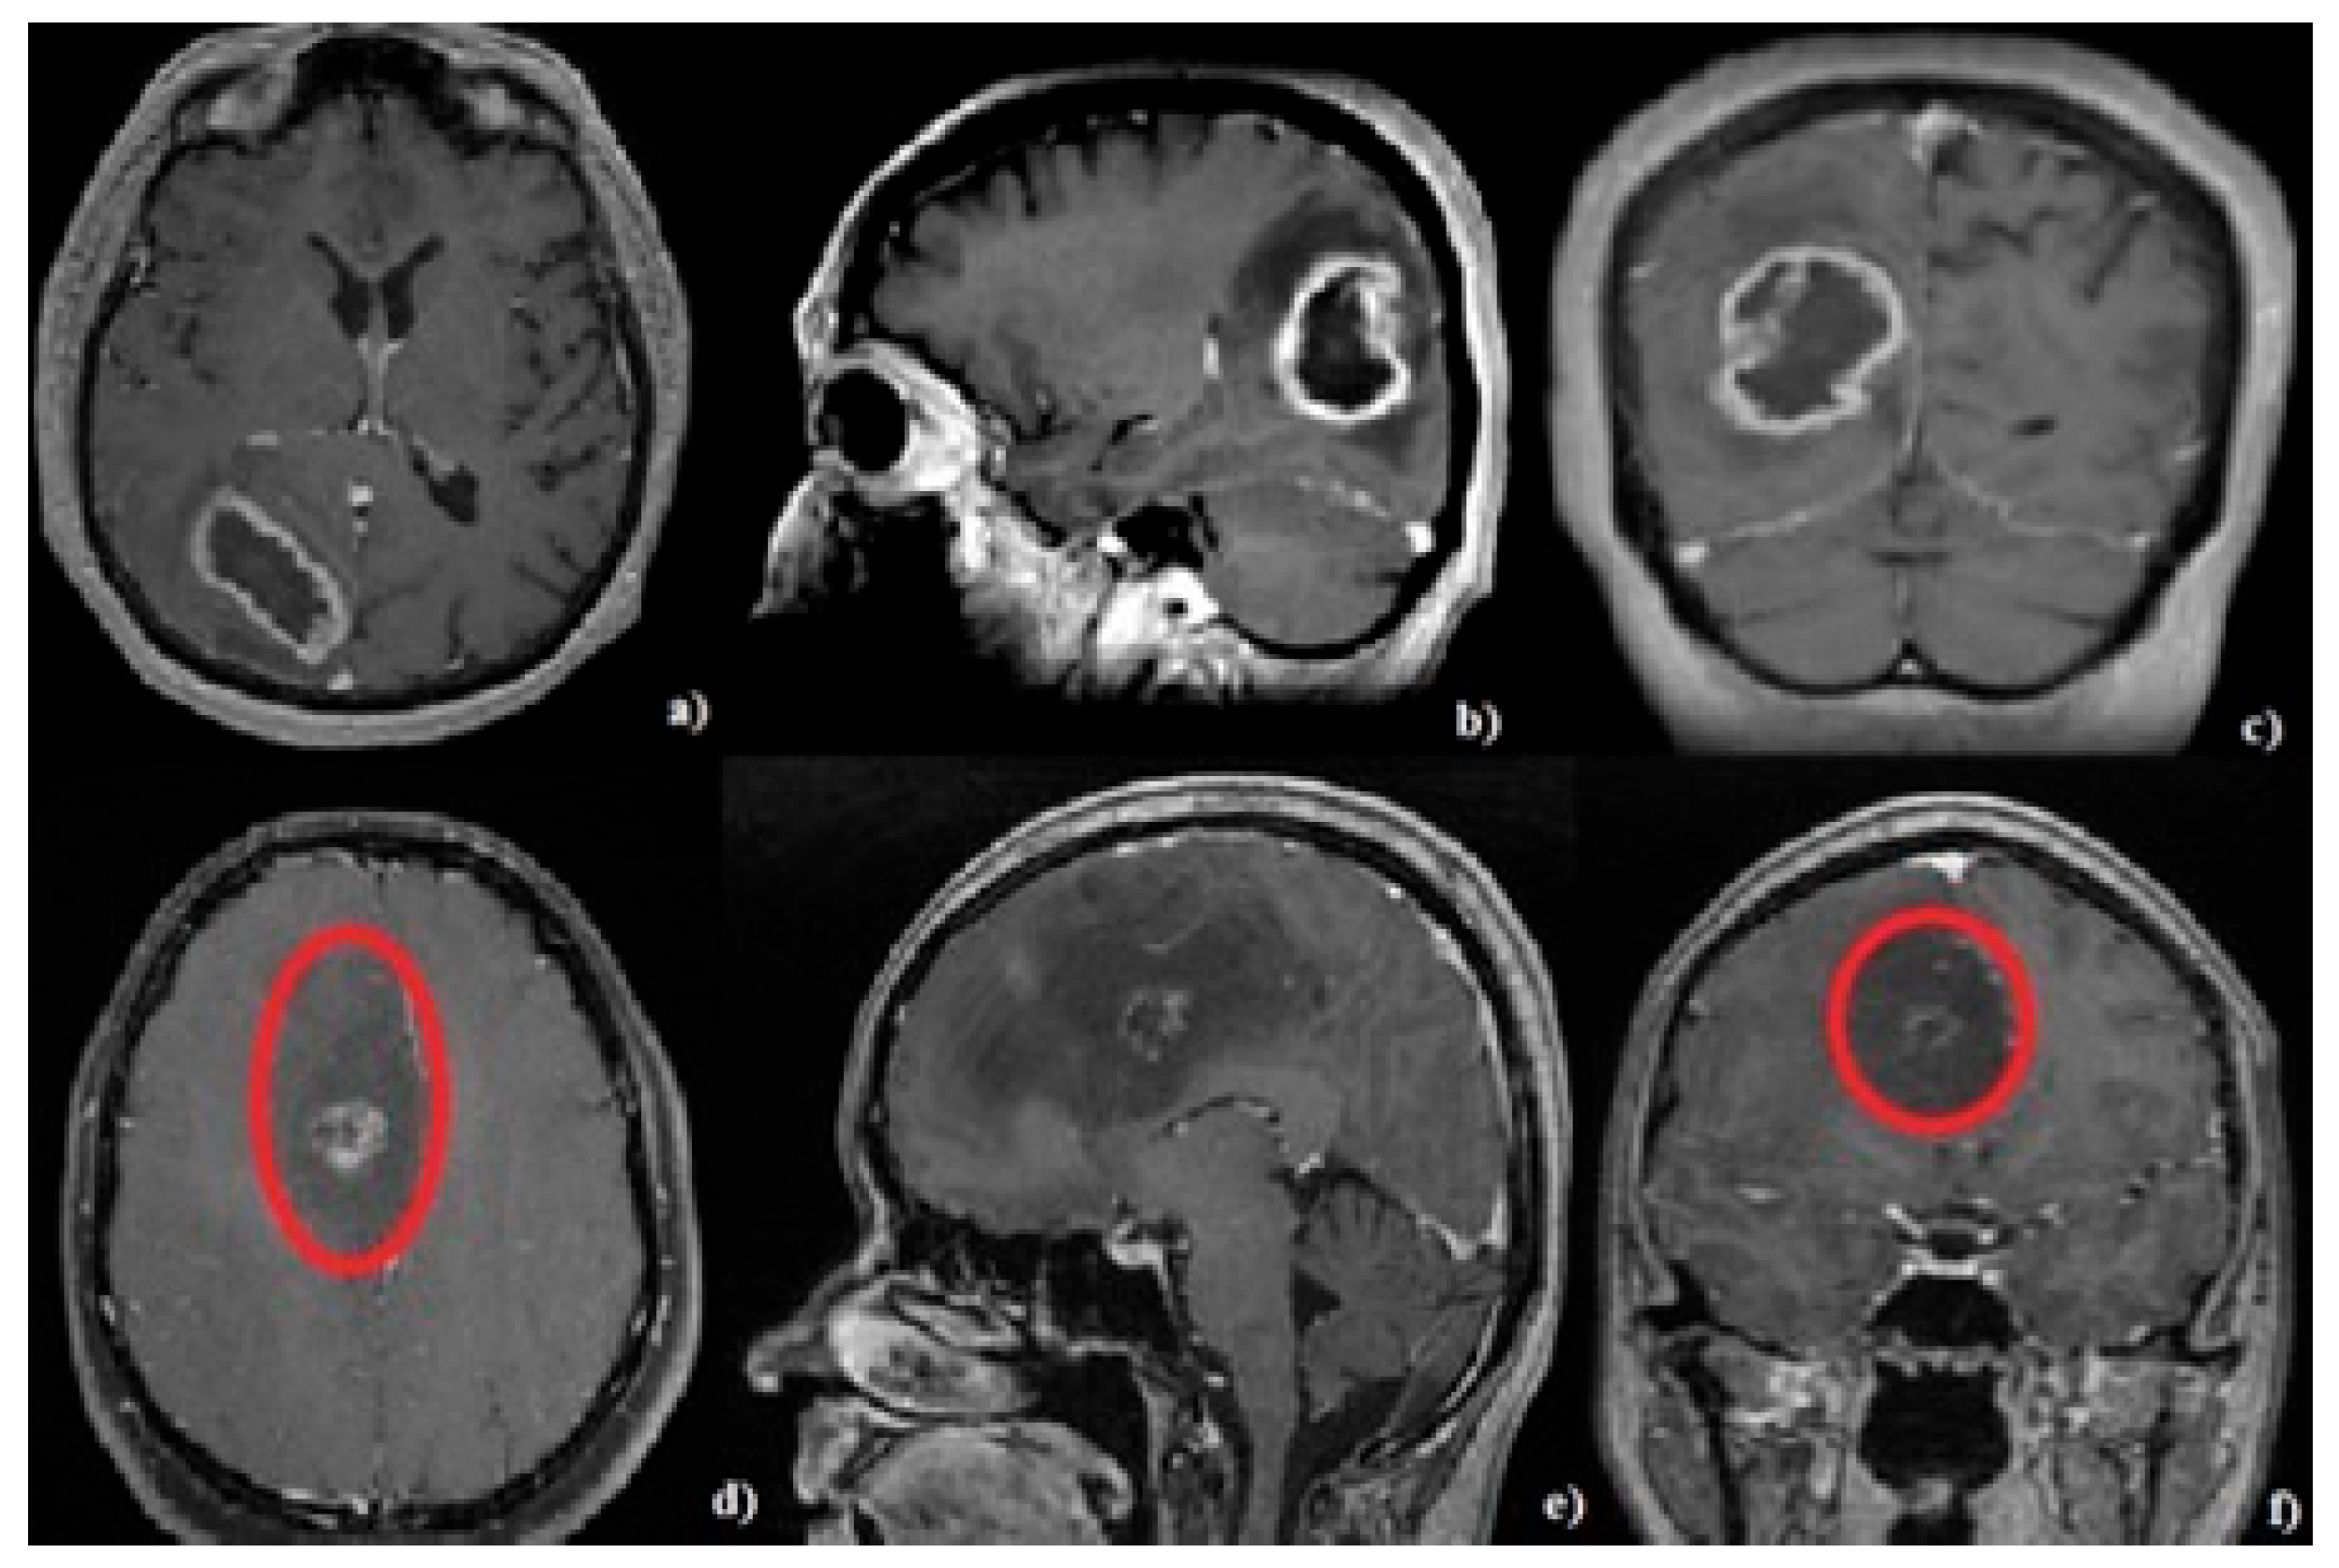

2.5. Neuroimaging Evaluation

3.3. Tumor Characteristics